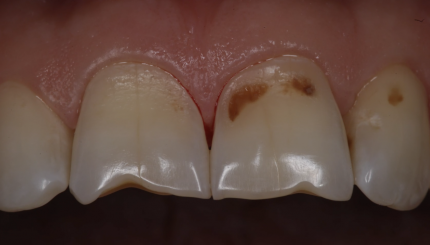

Препарирование дисколорированного 21+провизорная коронка

10 августа 2021